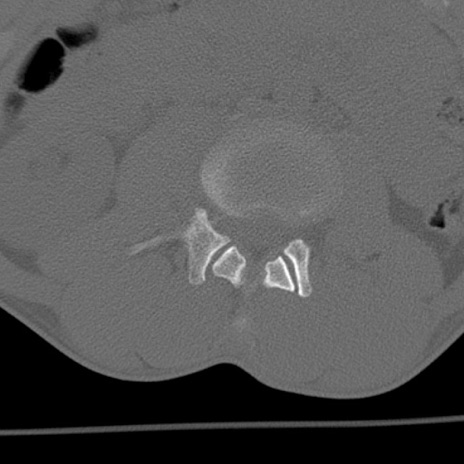

症例3 腰椎CT(横断像)

腰椎CT